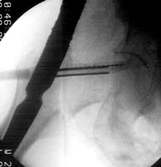

Position des Gerätes in seitlicher Lage ergibt beim Röntgen die folgenden Aufnahmen. Der geriffelte Draht liegt nicht zwischen den zwei glatten Drähten. Bewegen des Zielgerätes ergibt das erforderliche Bild. Sollten die so positionierten Drähte sich nicht über dem Kopf abbilden, muß der Nagel gedreht werden. Auf diese Weise erreicht man die korrekte Lage der Schenkelhalsschraube in die Mitte des Kopfes, ein Auswandern der Schraube ist so unmöglich.